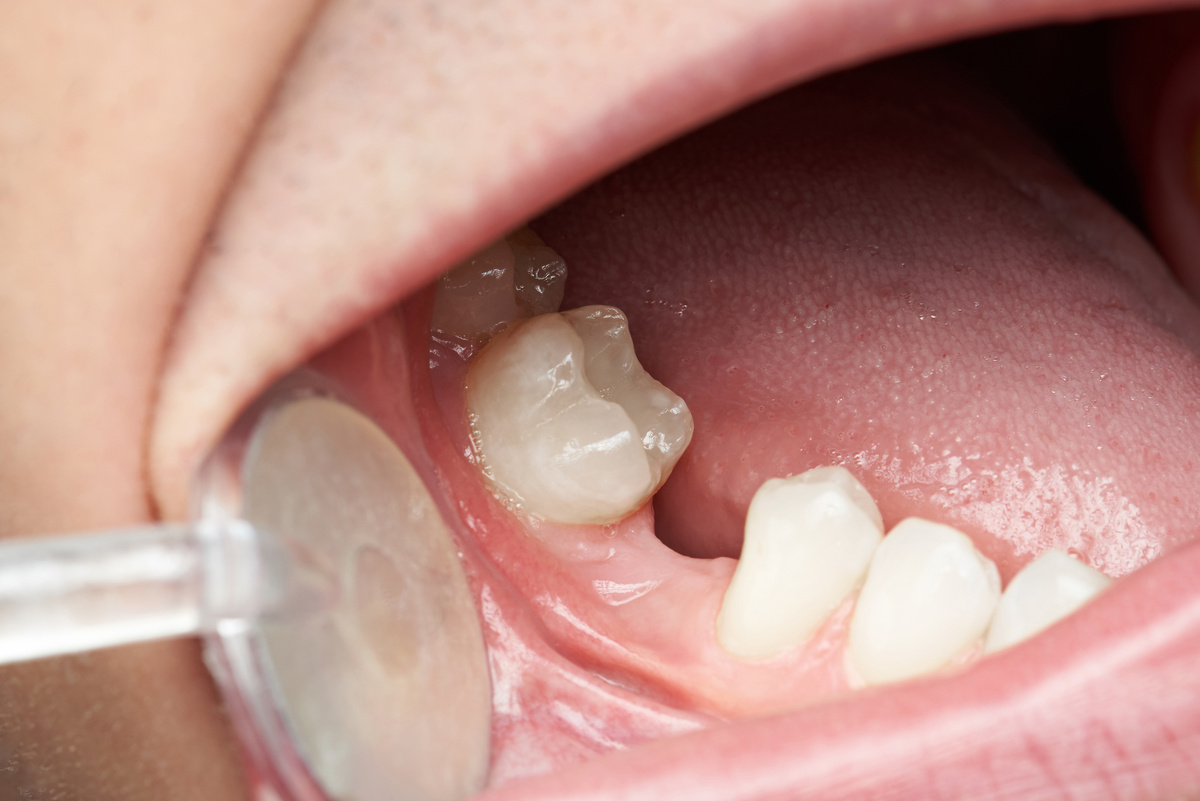

Getting a tooth extraction can leave your smile feeling incomplete, and you may wonder how long you’ll have to wait before restoring your confidence and your smile’s appearance with a dental implant. The answer depends on several factors, including the condition of your jawbone, your overall health, and the type of implant procedure that’s right for you. At Richard Hardt,